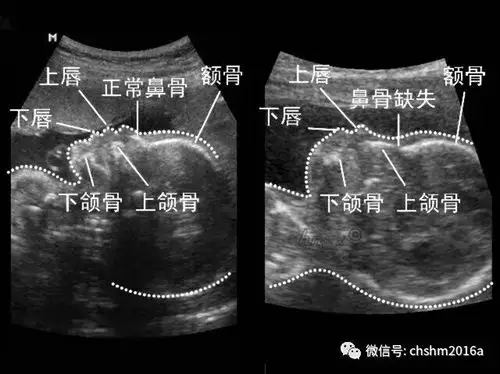

胎儿鼻骨缺失或不全,可不是生一个伏地魔那么简单

胎儿鼻骨缺失和或发育不良的医生专业指导

产科超声软指标

如何理智的对待孤立性鼻骨缺失